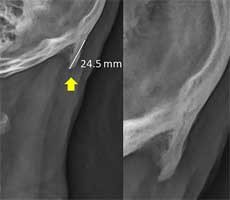

New research in biomechanics suggests that young people are developing horn-like spikes at the back of their skulls due to excessive mobile phone use. These bone spurs are reportedly caused by the forward tilt of the head, which shifts the weight from the spine to the muscles in the back of the head. That tilt is causing bone growth in the

Source: Hot Hardware – Researchers Say Horns Are Growing In The Back Of Human Skulls Due To Cellphones